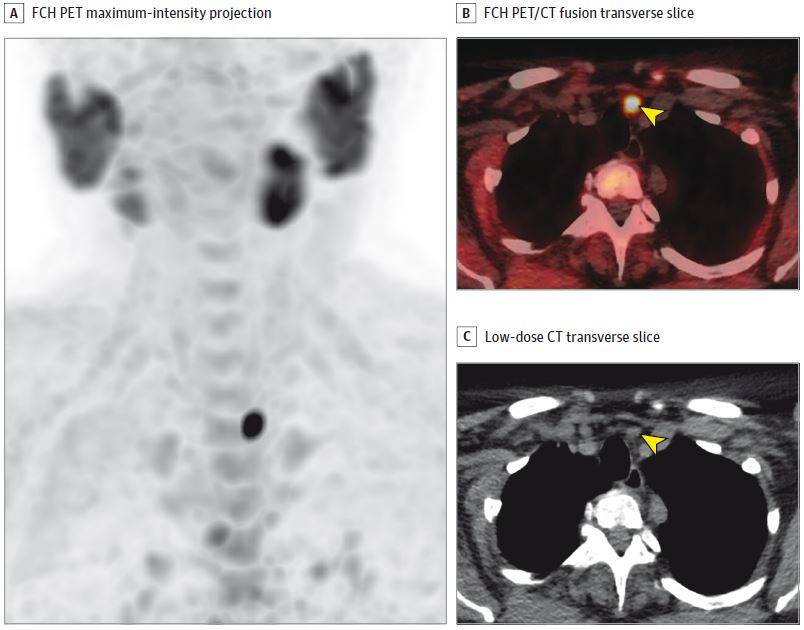

The procedure standards focus specifically on the technical aspects of somatostatin receptor (SSTR) ligands, which can be used in both PET imaging and treatment of meningiomas, and are meant to ensure effective use of the approach, noted lead author Nathalie Albert, of Ludwig Maximilian University in Munich.

Theranostics consists of using an imaging tracer for in-vivo visualization of a tumor-specific target, which is then addressed by the same or analogous molecule labeled with a therapeutic radionuclide instead of the diagnostic radionuclide.

- To assist healthcare professionals, particularly nuclear medicine practitioners, in recommending, interpreting, and reporting the results of brain SSTR-PET imaging in meningiomas.